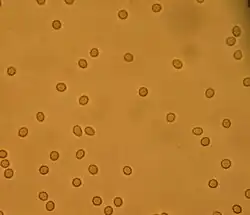

La orina en condiciones normales no posee sangre. Se acepta como máximo un número de 1 o 2 hematíes por campo en el sedimento de orina centrifugada,[1] o hasta 5 hematíes por campo en mujeres. Lo cual no produce cambios en la coloración de la orina, dado que la sangre se torna macroscópica cuando hay 100 o más hematíes por campo en el mayor aumento.

- Hematuria microscópica: el color de la orina es normal (amarilla), pero el examen de sangre en la orina es positivo. Hay pequeñas cantidades de sangre, visibles solo por uroanálisis o por un microscopio óptico. Aunque es posible que la tira química para el examen de la orina de falsos positivos, que son el resultado de, entre otros, la presencia de hemoglobina o mioglobina.

Los glóbulos rojos pueden proceder de los glomérulos renales. En este caso se someten a cambios durante el periodo de transición dentro de los túbulos renales, por lo que en el examen microscópico del sedimento urinario se ven hematíes mal conservados.[4] En este caso la hematuria glomerular por lo general es consecuencia de un daño al glomérulo, tal como una glomerulonefritis:

Los glóbulos rojos de los riñones pueden unirse entre sí y formar cilindros de sangre, lo que suele ser patognomónico de la hematuria glomerular y, por tanto, de la glomerulonefritis. El diagnóstico se basa en el interrogatorio que detecta las características del sangrado, la ecografía renal, que logra excluir otras causas, las características de los glóbulos rojos en el momento del examen microscópico del sedimento urinario. Un análisis más profundo puede requerir de biopsia renal.

Una causa igualmente rara de hemorragia es la necrosis de las papilas renales, fundamentalmente por el abuso de analgésicos y la anemia drepanocítica.[5] En los casos de ruptura de los quistes, el cáncer renal y la necrosis papilar, las células no suelen ser objeto de modificaciones durante el paso por los túbulos renales y, por tanto, normalmente se ven glóbulos rojos bien conservados bajo el microscopio.

La hipercalciuria (es decir, la excesiva eliminación de calcio en la orina) y la hiperuricosuria (es decir, la eliminación del exceso de ácido úrico en la orina) puede causar una insuficiencia renal con microhematuria, pero con glóbulos rojos bien conservados.[7][8] El diagnóstico es la determinación de calcio y ácido úrico en la orina emitida en 24 horas, después de excluir otras enfermedades con las investigaciones diagnósticas correspondientes.

El diagnóstico de hematuria debe hacerse por examen del sedimento de la orina, centrifugando la muestra recogida de inmediato después de la micción matutina. Normalmente, no se observan más de 2 hematíes por campo microscópico (a gran aumento).[9]